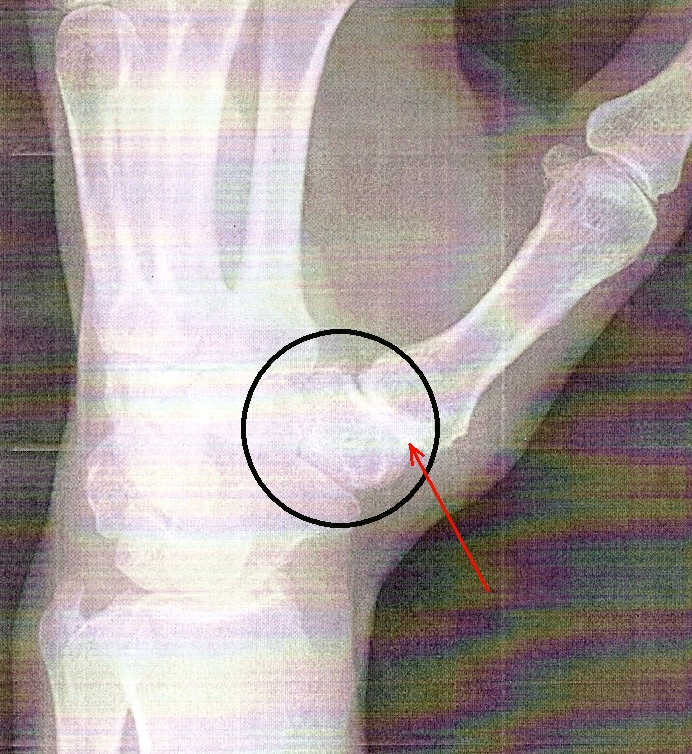

There's a cube-shaped bone at the base of the thumb called the trapezium. I had developed arthritis in the joint between the trapezium and the first bone of the thumb, which means the cartilage on the facing surfaces of those bones had worn away.

You can see the arthritis in this x-ray because there is no space between those two bones (red arrow). The cartilage that separates two bones will show up as a space between the bones in an x-ray because it isn't as dense as bone. As you can see, there's no space here. There was bone-on-bone contact. The surgery was on June 6th, 2014. |